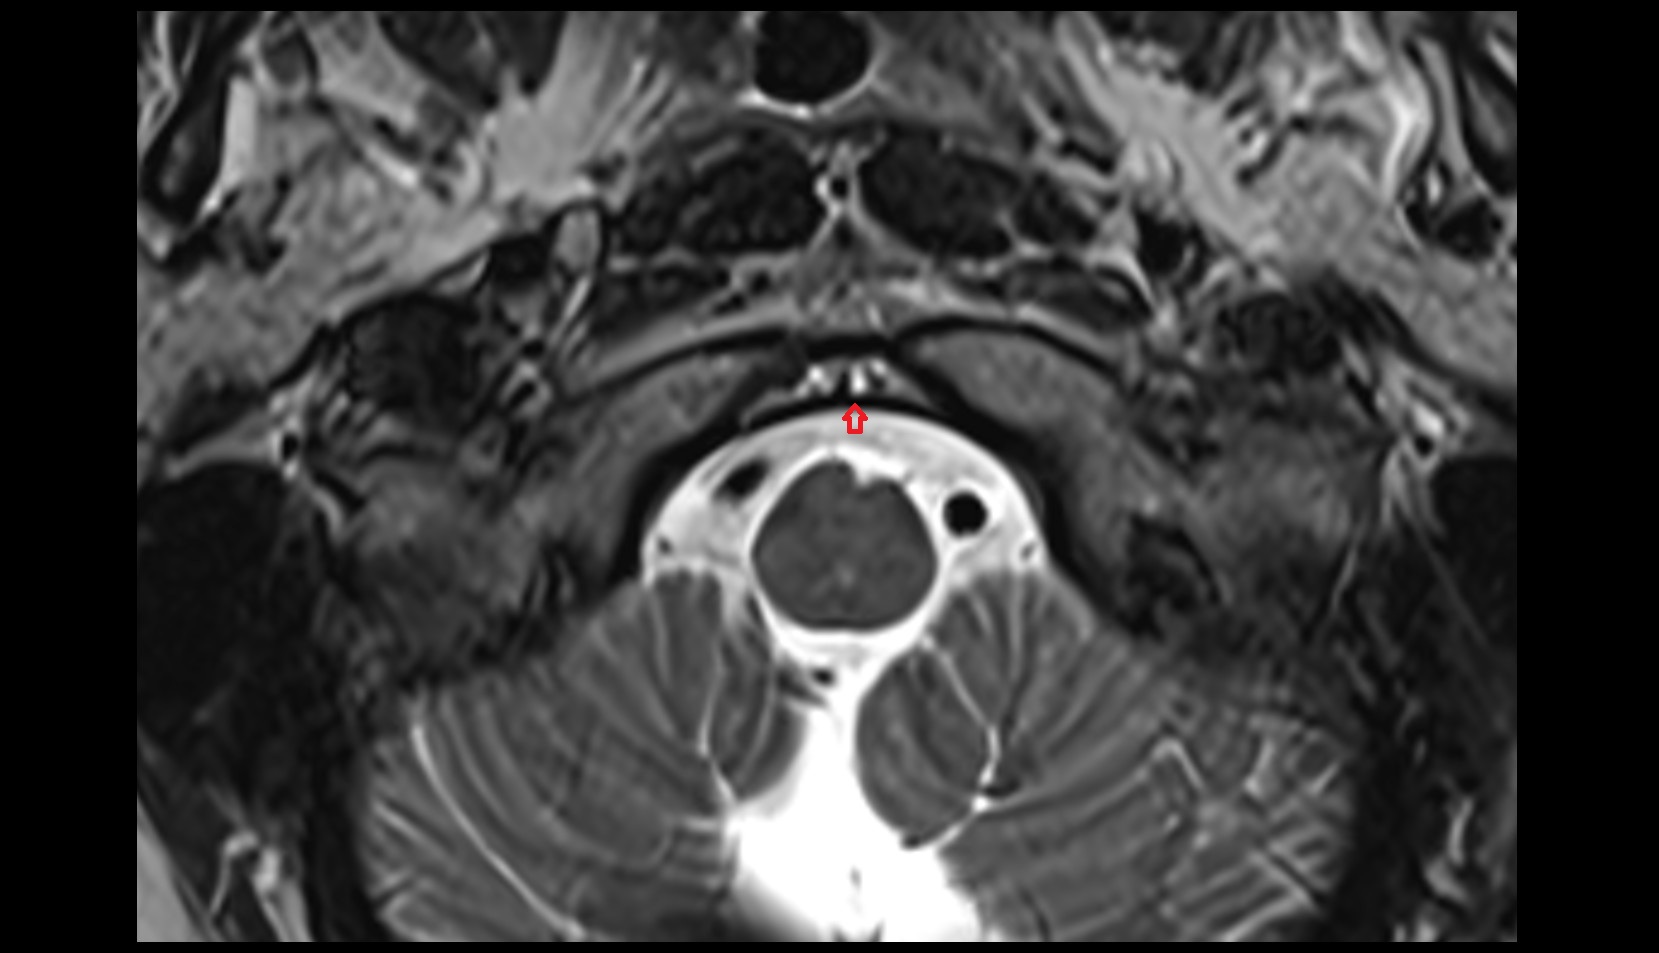

- Upper cervical spinal cord

- Spinal cord